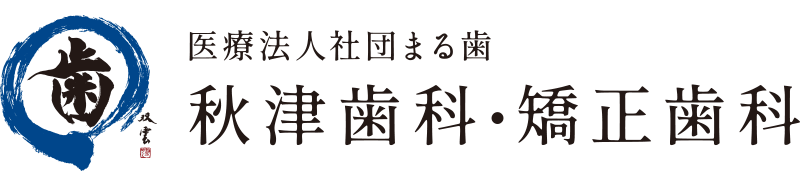

根管治療とは

根管治療とは、虫歯菌が神経まで達し、感染した根管をキレイに洗浄を行い、最終的に再感染を防ぐために根管内を詰める治療です。

根管治療は「管」の汚れを取る治療です。これは排水管の中を綺麗に掃除するのと同じです。

根管充填

根管内部がキレイになり、目立った症状が消失したら、根管の内部を生体親和性のある材料をつめて再感染を防止します。